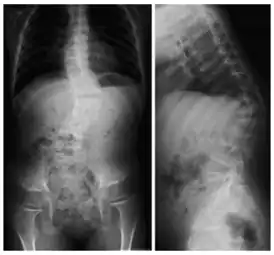

![]() Рентгеновский снимок позвоночника пациента с кифосколиозом. На проекциях хорошо видно искривление позвоночного столба вбок (сколиоз) и выпуклостью назад (увеличенный кифоз) | |

Кифосколио́з (греч. kύφο – согнутый, горбатый и греч. σκολιός – кривой, лат. scoliōsis) – патологическое искривление позвоночника в сагиттальной и фронтальной плоскости, то есть одновременно в переднезаднем и боковом направлениях. Кифосколиоз сочетает в себе два заболевания – кифоз и сколиоз. Может быть как врождённым, так и приобретённым.